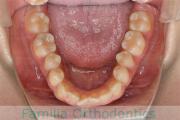

No.23V-100

- 上顎前突

- 叢生

- 14歳

- 女性

- 上:

- 44

- 下:

- 55

- 主な使用装置:

- FEA

歯並びを治したいということで来院されました。下あごがやや右側に偏位して後退している、上顎前突(出っ歯)でした。上下左右から小臼歯を抜歯して、歯科矯正用アンカースクリューを併用したマルチブラケット法にて治療を行いました。約2年、24回の来院をしていただきました。

下顎の後退はいびきなどの上部気道の障害が出やすいと考えられます。